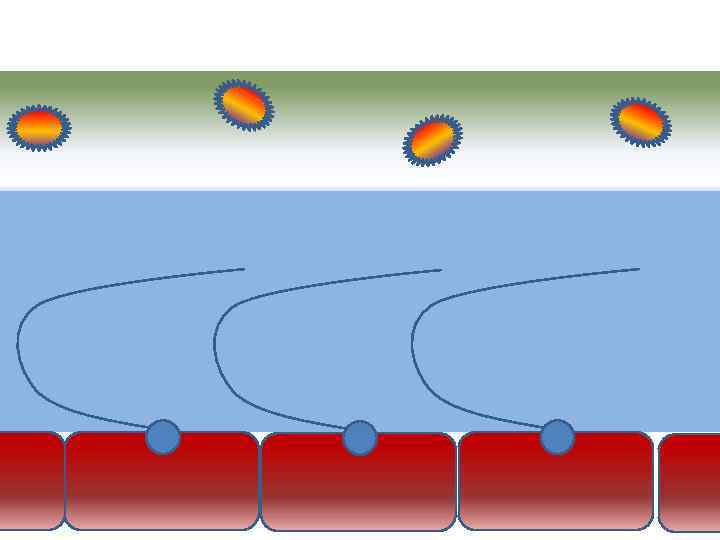

Движение клеток реснитчатого эпителия Движение вперед 1 – 3 Обратное движение 4 – 8

Движение клеток реснитчатого эпителия Движение вперед 1 – 3 Обратное движение 4 – 8

Оптимальное увлажнение Достаточная продукция слизи Хороший транспорт Экономит энергию и воду Защитная функция

Оптимальное увлажнение Достаточная продукция слизи Хороший транспорт Экономит энергию и воду Защитная функция

Механизм защиты легкого Слизь (зеленый цвет) нейтрализует и связывает патогенную флору(синий цвет) Слизь – это барьер между клетками и патогенной флорой Слизь – это транспортное средство

Механизм защиты легкого Слизь (зеленый цвет) нейтрализует и связывает патогенную флору(синий цвет) Слизь – это барьер между клетками и патогенной флорой Слизь – это транспортное средство